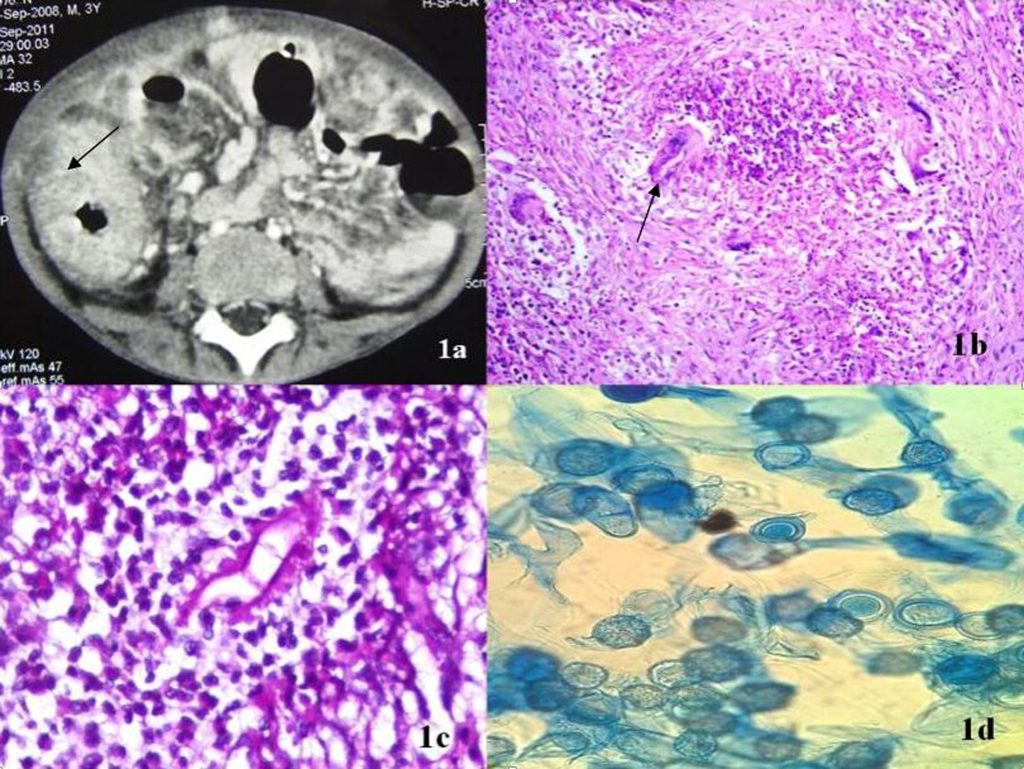

Pasien biasanya menunjukkan benjolan keras, berwarna merah, dengan ukuran yang bisa bertambah besar secara perlahan. Pada kasus ini, seorang gadis berusia 14 tahun mengalami benjolan di paha kanannya yang semakin membesar selama tujuh bulan. Gejala ini kadang disalahtafsirkan sebagai tumor, radang, atau infeksi lain seperti tuberkulosis kulit. Ciri khas dari basidiobolomycosis adalah adanya benjolan yang keras dan tidak nyeri, seringkali tidak menunjukkan gejala lain seperti demam atau nyeri. Pada pemeriksaan mikroskopis, ditemukan struktur jamur besar yang dikelilingi oleh deposit eosinofilik yang disebut fenomena Splendore-Hoeppli, yang merupakan tanda khas infeksi ini. Pemeriksaan kultur jamur juga memperkuat diagnosis dengan menunjukkan organisme Basidiobolus. Infeksi ini sering terlambat terdiagnosis karena gejalanya mirip dengan kondisi lain seperti granuloma, abses, atau tumor. Jika tidak ditangani segera, infeksi dapat menyebar ke jaringan yang lebih dalam dan menyebabkan deformitas atau kerusakan jaringan yang permanen.